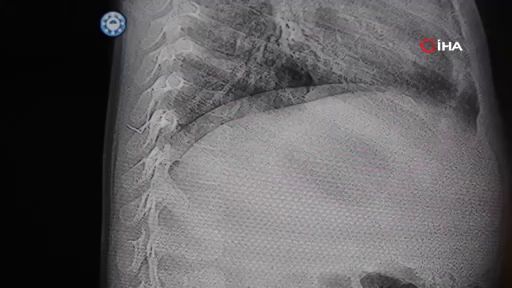

Kahramanmaraş’ta sırt üstü yatmak istemeyen ve yatırıldığında sürekli ağlayan bir yaşındaki bebeğin sırtında, akciğer zarına doğru ilerleyen yaklaşık 2 santimetre uzunluğunda metal bir tel parçası bulundu. Zımba teline benzer tel, gerçekleştirilen başarılı operasyonla çıkarıldı.

Ailenin çeşitli hastanelerde yaptığı başvurulara rağmen bebeğe müdahale edilmedi, hatta bazı kliniklerde yabancı cismin alınması için 8 yaşına kadar beklenmesi gerektiği bildirildi. Bunun üzerine aile, son çare olarak HG Hospital’a başvurdu.